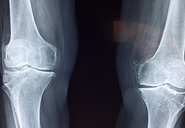

비타민d 부족증상 효능 하루 적정량 등 비타민 d에 대해 알아보도록 하겠습니다.비타민 D는 태양에서 받은 자외선을 통해 피부에서 합성되며, 섭취할 수 있는 식품에서도 일부 함유됩니다. 칼슘과 함께 작용하여 골의 건강을 유지하는데 중요한 역할을 합니다. 또한 면역 기능을 강화하는데도 효과적이며, 심각한 결핍증은 골다공증, 뼈 연화증 등을 유발할 수 있습니다. 하지만 과도한 섭취도 유해하며, 개인에 따라 적절한 섭취량은 다를 수 있습니다. 충분한 양의 비타민 D를 섭취하기 위해서는 태양에 노출되는 것과 함께, 식사나 보충제를 통해 섭취하는 것이 좋습니다.

- 골다공증: 비타민 D 부족은 골의 밀도가 감소하여 골다공증의 원인이 될 수 있습니다.

- 뼈 연화증: 비타민 D 부족은 뼈의 결손성 발달을 촉진하여 뼈가 약해지고 쉽게 부러지게 만들 수 있습니다.